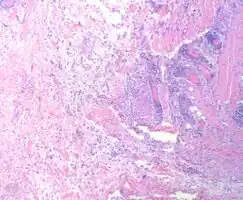

Myxofibrosarcoma-pathology